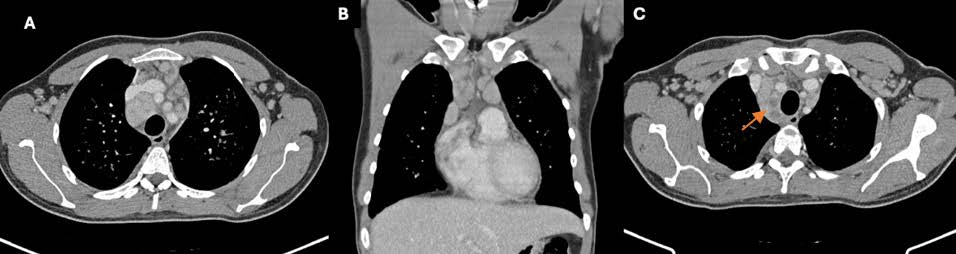

A chest radiograph (Figure 1) and a thoracic computed tomography (CT) were performed, revealing multiple bilateral solid and subsolid nodules, ill-defined and with varying sizes (not exceeding 1 cm), with a tendency to confluence and mostly with a peribroncovascular pattern of distribution, although some juxta-pleural nodules were seen (Figure 2). Additionally, a consolidation on the middle and right lower lobe with air-bronchogram was identified (Figure 2). Multiple enlarged mediastinal and hilar lymph nodes were also present, some with central hypodensity suggestive of necrosis (Figure 3). Pleural effusion was excluded.